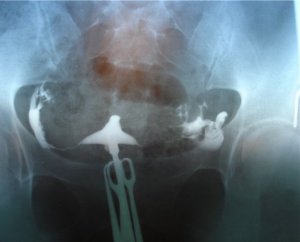

На снимке частичная непроходимость маточных труб

Процедура позволяет обследовать полость матки и выявить полипы, эндометриоз. Достоверность результатов составляет около 80 %, но в сочетании с другими методами и, дополняя анализами, можно с точностью поставить окончательный диагноз:

- На изображении можно четко проследить, как контрастное вещество останавливается на определенном отрезке трубы. Если трубы склеяны спайками, то контраст будет растягивать ампулярную часть. При смешивании контрастного вещества с экссудатом отчетливо прослеживается колбообразная ампулярная часть трубы. В результате выявляют сальктосальпинксы.

- Если жидкость беспрепятственно проходит в маточные трубы, то это свидетельствует о нормальной проходимости. При этом на снимке будет видно, как контрастное вещество вышло в брюшную полость.

- Если контраст остался в матке, то это явный признак непроходимости маточных труб.

- В норме форма матки имеет вид перевернутого прямоугольника, полностью окрашенного контрастом. Если полость матки изменена, маленького размера и деформирована, то это указывает на запущенную форму туберкулезного эндометрита.